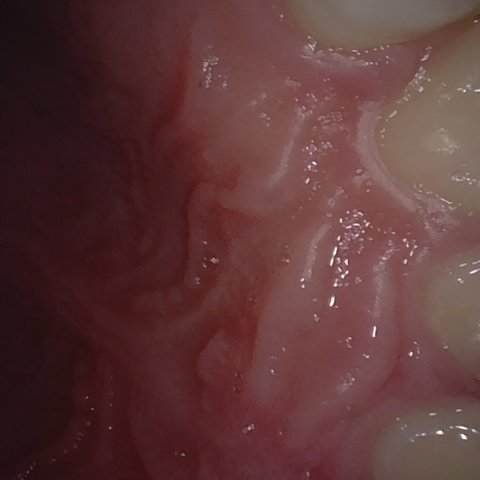

NHD39990

Annotated as "Good"

Original Image Rendering Image